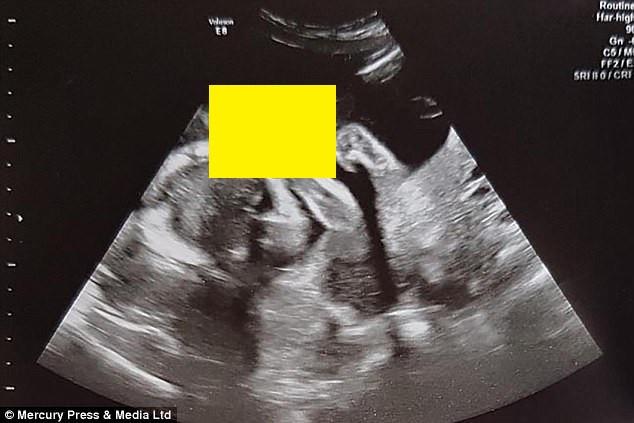

Mesajul Transmis De Un Bebeluș Nenăscut La Ecografie I A Speriat